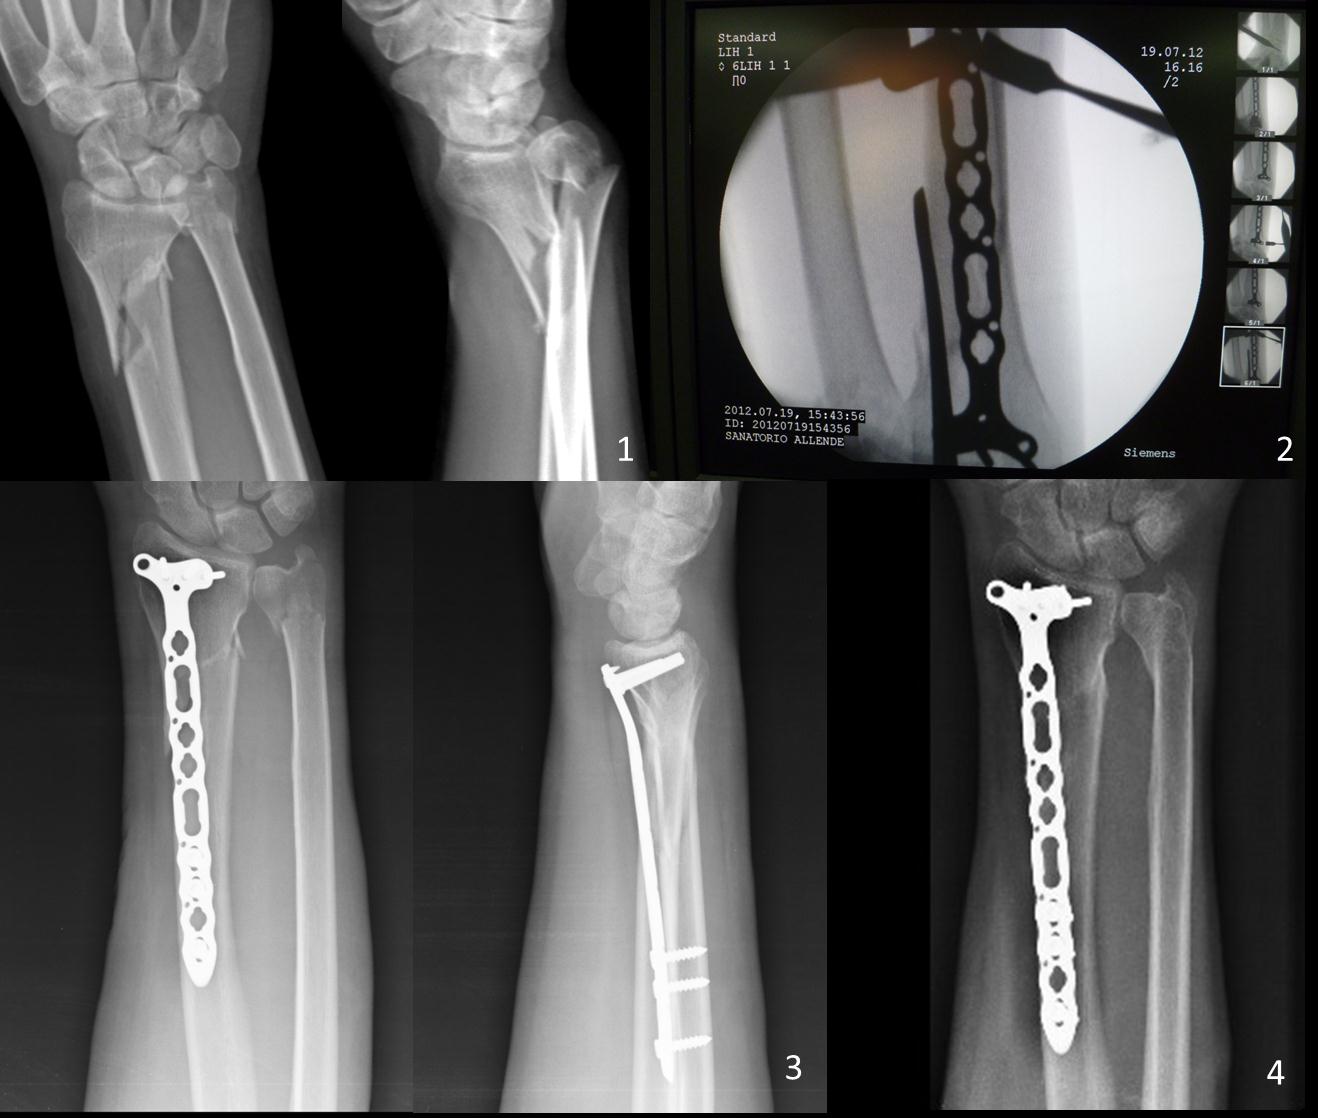

Introduction: Purpose:To evaluate objective and subjective outcomes after closed reduction and minimally invasive volar locked T plate osteosynthesis for distal radius fractures with metaphyseal involvement.MethodsWe retrospectively evaluated six patients treated by minimally invasive volar locked T plate osteosynthesis for unstable extra-articular or partial articular distal radius fractures with metaphyseal involvement between 2007-2012. Age averaged 40, 6 years. All were closed fractures classified as type 23A3 (n: 5) and 23B1 (n: 1) according to the AO/OTA system.  Indirect reduction was performed. Two volar small incisions were made; a volar locked compression T plate was introduced in the sub-muscular plane, under radioscopic guidance. Analysis included radiological parameters (volar angulation, radial inclination, and radial height); range of motion and strength. Subjective results were assessed using DASH Score and Visual Analogue Scale.ResultsAll fractures healed within 2, 3 months. Radiographic outcomes showed no difference between the first postoperative control and the last Rx at one year of follow up. Flexion and extension averaged 70° and 60°, pronation and supination 79° and 80°. Grip Strength 78, 4%. DASH Score 19, 84 and VAS 1, 5 points.ConclusionsMinimally Invasive technique decrease surgical injury and complications (infections and re fractures). It is an option in patients with metaphyseal comminution severe soft tissue injuries and high energy trauma. Small incisions away from the fracture site preserve soft tissues, bone biology and improve healing. Percutaneous volar LCP allows obtaining stable fixation and restoring distal radius anatomy in radius fractures with metaphyseal involvement. It is technically demanding procedure. The most common problem is bone misalignment.